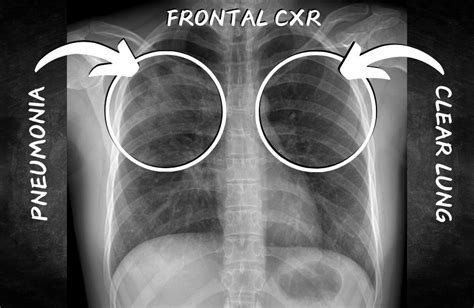

Radiologists examine various aspects of a side view chest X-ray to diagnose pneumonia. These include looking for opacities (whiteness) which indicate fluid or inflammation in the lungs. The location and shape of these opacities can help determine the type and extent of pneumonia. They also assess the clarity of lung markings, which can be obscured by the infection.

While frontal chest X-rays are commonly used, side view (lateral) X-rays provide crucial additional information. They offer a different perspective on the lungs, allowing radiologists to see areas that might be obscured in the frontal view. This is especially important for identifying pneumonia located behind the heart or near the spine.

Frontal view X-rays provide a broad overview of the lungs and surrounding structures. They are typically the first imaging study performed in suspected pneumonia cases. These images allow doctors to quickly assess the size and shape of the lungs, the position of the heart and diaphragm and identify any obvious abnormalities.

However, certain areas of the lungs can be obscured by the heart and other structures in the frontal view. This makes it challenging to detect pneumonia located in those regions. This is why side view X-rays are often necessary for a complete evaluation.

Side view X-rays offer a different perspective, revealing areas hidden in the frontal view. This allows for a more comprehensive assessment of the lungs, especially regions behind the heart and near the spine. This perspective is vital for accurate pneumonia localization.